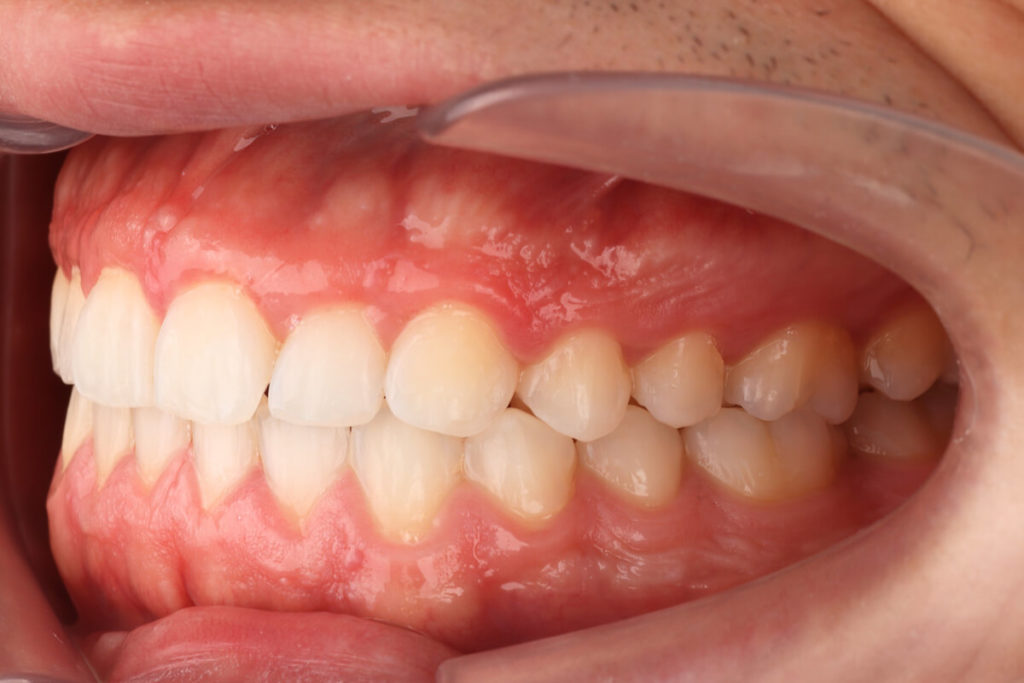

SITUACIÓN FINAL

Se resuelve el apiñamiento, la relación entre los caninos y los molares de clase I, y se estabilizan el overjet y el overbite. Corrección del desplazamiento de la línea media. En el paso final se realizó un blanqueamiento y restauraciones directas en los dientes 12 y 22 .

Colocamos retención fija en el maxilar inferior y retenciones removibles tanto en superior como en inferior.